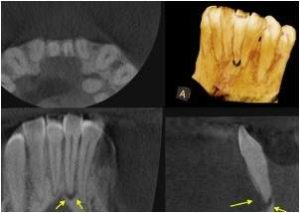

Cone Beam CT Scanner

Raymond is one of the only endodontists in Fulton County to utilize Cone Beam CT technology in his office. Our Kodak 8100 3D scanner allows us to take high-quality three-dimensional images of your condition, thereby providing you with more targeted, more precise, and more effective treatment. Cone Beam CT scans are only taken when necessary, and the benefits of them are innumerable:

- Three-dimensional Cone Beam CT scans allow Dr. Raymond to better detect, locate, and treat endodontic conditions, such as abscess formation, resorption, and complex anatomy.

- Unlike a conventional dental x-ray, a Cone Beam CT scan can distinguish the differences among various tissues, such as bone, teeth, nerves, and soft tissue.